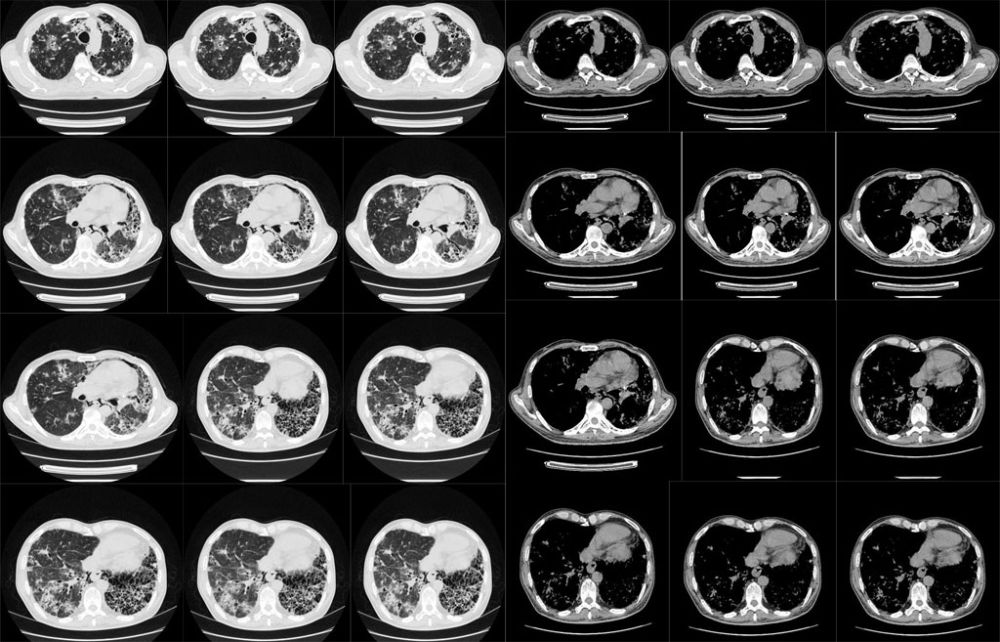

男,61岁,呼吸困难1周,以前病史不详,行ct检查:

双肺感染性病变,以结核可能性大,左下肺可见多个囊状低密度,不除外支扩(病史不相符)。

双肺多发斑片状、磨玻璃影,左肺呈蜂窝状改变,右肺多发空洞伴结节,考虑1支扩2间质性肺炎

肺泡癌可能。

两肺感染性病变,不除外肺泡癌,建议抗炎治疗后复查。